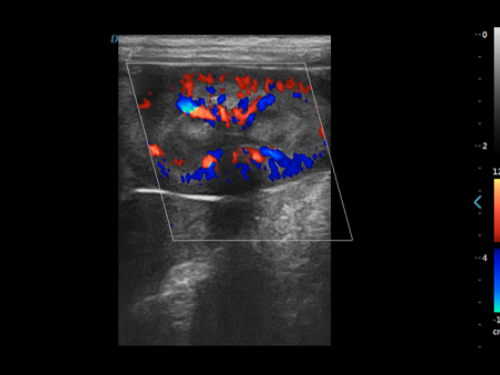

颈动脉血流:颈动脉彩超是诊断、评估颈动脉壁病变的有效手段之一,在动脉粥样硬化的流行病学调查和对动脉粥样硬化预防、治疗试验的有效性评价中起着关键作用。 颈动脉彩超不仅能清晰显示血管内中膜是否增厚、有无斑块形成、斑块形成的部位、大小、是否有血管狭窄及狭窄程度、有无闭塞等详细情况, 并能进行准确的测量及定位,还能对检测动脉的血流动力学结果进行分析。